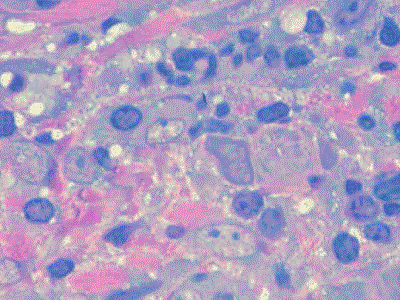

El epitelio de unión y el epitelio de la bolsa son muy permeables  a moléculas grandes que activan una reacción inmune en el tejido conjuntivo gingival . En las fases tempranas en  esta reacción predominan los linfocitos para luego aparecer las células plasmáticas  y en forma tardía predomina la infiltración inmune. La reacción inmune genera los mediadores que refuerzan la inflamación y el daño al tejido. En particular la producción de citoquinas  es prominente. Estas substancias son moléculas muy  potentes que activan varios  eventos perjudiciales  en el tejido conjuntivo.

La inflamación  y las reacciones inmunes de la gingiva y el periodonto resulta en que dichas estructuras funcionales son reemplazadas por tejido de granulación, que continúa creciendo apicalmente,  facilitando el desarrollo de placa bacteriana en la bolsa periodontal.